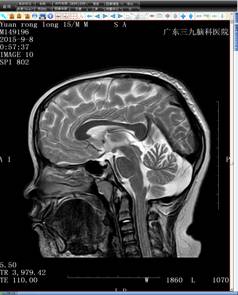

结合小袁的病史,神经内二科的钟水生主任考虑其存在垂体柄阻断综合征的可能(图一),并建议补充垂体薄层平扫+增强扫描(图二)。完善检查后,钟主任给予小袁B族维生素、申捷促进神经修复等对症治疗。

头颅MRI T2+FLAIR+增强(图二)

4、MRI特征性影像表现包括:垂体柄的完全性缺如或明显变细,T1WI垂体窝后部正常或垂体后叶于第三脑室漏斗隐窝或正中隆起处可见到异常垂体后叶的小斑片状、小结节状高信号,这是PSIS的特异性征象,也是诊断要点;垂体前叶不同程度萎缩变薄,结构显示不清,甚至消失。